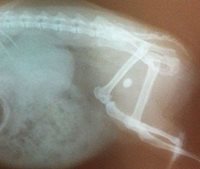

We hebben Willemien daarom laten terugkomen op de praktijk in Sittard. Daar is er een röntgenfoto gemaakt. Gelukkig zagen we al snel wat het probleem was, er zat namelijk een steen in de blaas van Willemien! Tussen de achterpootjes is duidelijk een wit rondje te zien. Dit is de blaassteen.

Eenmaal daar aangekomen, wilde de dierenarts een rontgenfoto maken van de blaas omdat het nog wel eens voorkomt dat een cavia steentjes ontwikkeld in de blaas. En ja hoor, een grote, witte vlek op de foto t.h.v. haar blaas gaf gelijk duidelijkheid: een blaassteen!